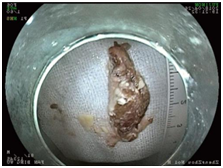

经过紧张的准备,手术顺利实施。手术过程中发现在食管距门齿17厘米处,也是食管上段最狭窄的地方,一颗大枣核嵌顿,枣核两端已深深扎入食管壁内。

经过努力,谢立群最终将枣核顺利取出,目前,范大爷已正常饮食,择日出院。